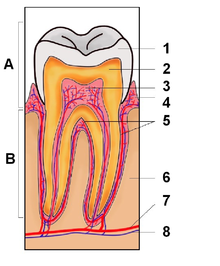

Τομή ενός ανθρώπινου δοντιού:

Α. Μύλη,

Β. Ρίζα,

1. Αδαμαντίνη,

2. Οδοντίνη,

3. Πολφός,

4. Ούλα,

5. Οστεΐνη,

6. Οστό της γνάθου,

7. Φατνιακά αγγεία,

8. Φατνιακά νεύρα